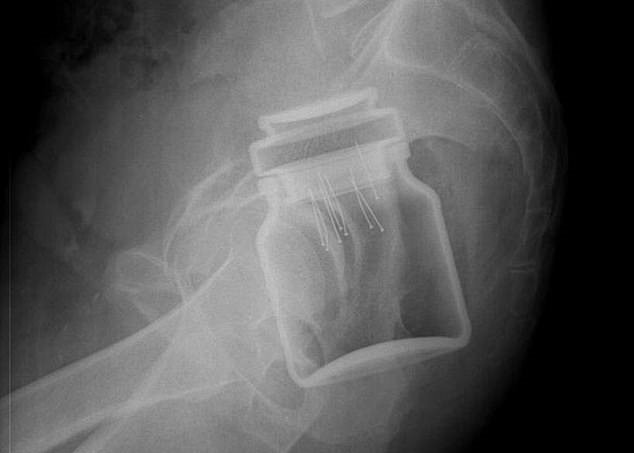

Every year, Americans end up with different types of objects stuck in their rectums.

It was found that the rectum is the most common place for bizarre items to get stuck. Some of the objects include household items such as aerosol can, plastic pill bottle, beer bottle, and a plastic cigar holder.

Other articles such as a ‘leg of a telescope’, ‘cell phone’ and ‘Christmas ornament ball’ have also been found in some patients.